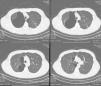

Presentamos el caso de un varón de 27 años con antecedentes personales de tabaquismo activo, fumador de 15 cigarros/día desde hacía 12 años, así como fumador habitual (3 cigarros/día) de marihuana, que ingresa en nuestro hospital por traumatismo torácico en relación con accidente de tráfico, motivo por el cual se le realizó una TC de tórax sin contraste intravenoso de urgencia, en la que se apreciaron bullas apicales y paramediastínicas bilaterales de predominio derecho, destacando una bulla de gran tamaño (13×11cm) en el segmento apical del lóbulo superior derecho (LSD) y algunas áreas de destrucción parenquimatosa en la región subpleural del LSD (fig. 1).

Bullas apicales y paramediastínicas bilaterales de predominio derecho. Destaca una bulla de gran tamaño (133×115mm) en el segmento apical derecho. Se identifican también algunas áreas de destrucción parenquimatosa en la región subpleural de lóbulo superior derecho, pequeñas bronquiectasias en el segmento apicoposterior del lóbulo superior izquierdo, y atelectasias subsegmentarias bibasales.